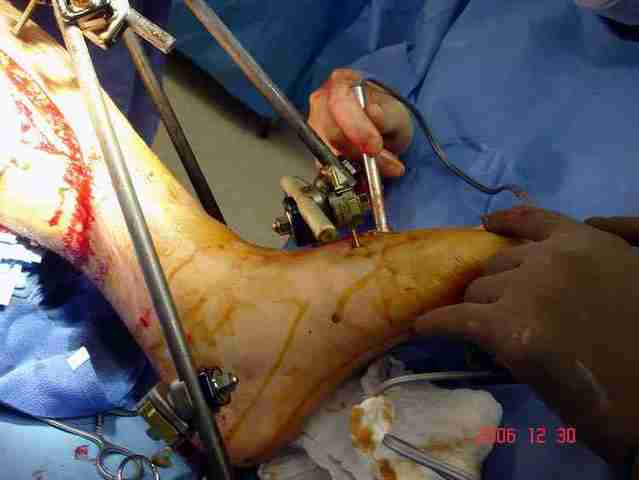

При высокоскоростных переломах редко можно встретить изолированную травму пилона, и в моей практике изолированные травмы большая редкость, поэтому, как дополнение к обсуждаемой теме, решил представить свежий, двухдневной давности случай.

Предыдущей сменой до 4:00 утра по поводу открытого перелома бедра, тибиал плато, пилон и надколенника сделана операция.

Пострадавшему 21 г., травма скоростная, после I&D с расширением раны, на бедре сделана операция ретроградным интрамедуллярным штифтом, остеосинтез с частичной резекцией надколенника и ушивание собственной связки.

На голень наружный фиксатор, рану на бедре ушили (рана была изнутри кнаружи всего 2 см). По протоколу травматических больных, до операции обследован ангиографически, (у больного дистально не смогли определить пульсацию) сосудистый хирург подтвердил проходимость на всем протяжении магистрального сосуда нижней конечности по снимкам ангиограмм.

В настоящее время больной в реанимации по поводу Черепно Мозговой Травмы и состояние улучшается. Запланировал ушивание раны в пятницу, если позволит состояние мягких тканей и при отсутстви отека возможно удастся просунуть перкутанномедиальную пластину.